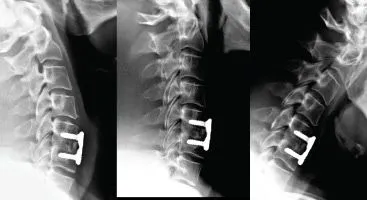

Neck and arm pain BEFORE and AFTER neck fusion surgery

Kevin had neck fusion surgery in November 2012. Following the surgery, he continued to have severe neck pain and stiffness.